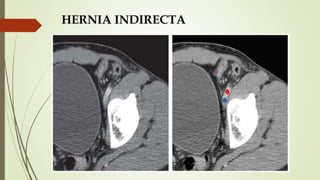

HERNIA INDIRECTA

 Pasa superolateral a vaso epigástrico inferior  lateral y medial

siguiendo el CI

 Se muestra con el contenido habitual del CI, no se comprime ni

distorsiona